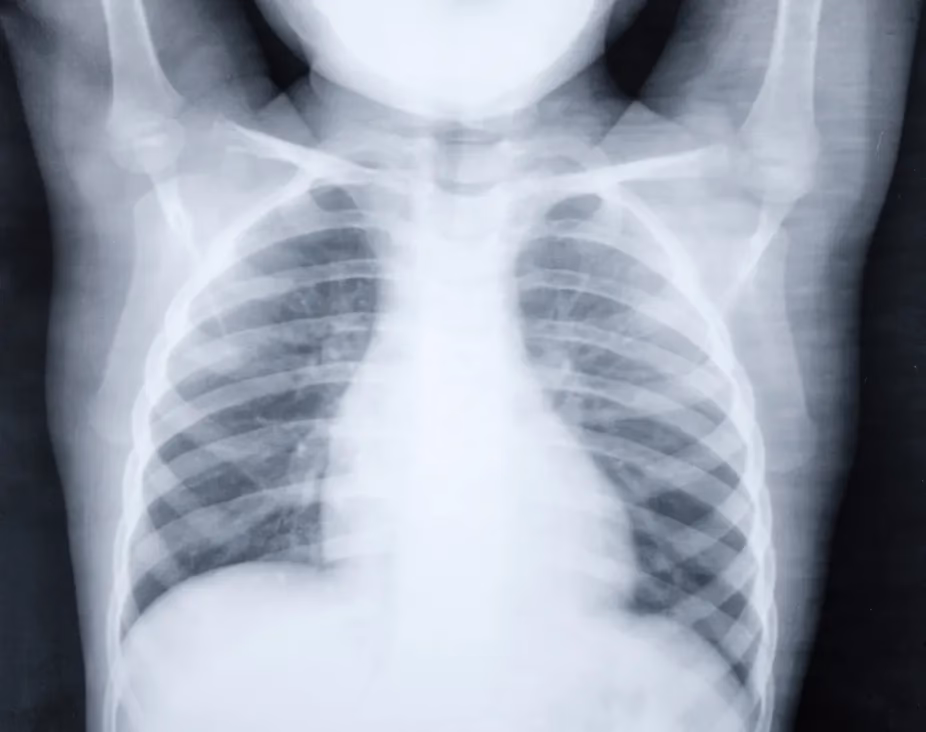

- Røntgenbillede af lungerne: Anvendes ikke rutinemæssigt, men kan være nødvendigt ved alvorlig sygdom, manglende bedring på behandling, eller hvis der er mistanke om komplikationer.